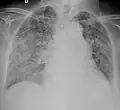

A case of miliary tuberculosis in an 82-year-old woman:

X-ray, 13 days after onset, showing bilateral interstitial infiltrates -